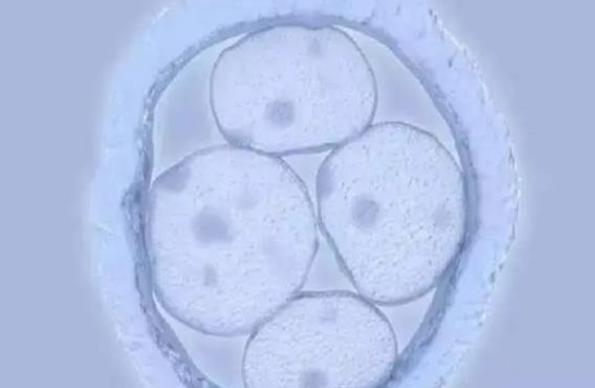

在传统试管婴儿技术中,医生会取出女性的卵子和男性精子,在助孕进行人工授精后再将怀孕卵移植回民主。而第三代试管婴儿则采用了更加前沿、精准和安全的方法。其中"ICSI",即单精子注射技术,可以直接将单个健康三代试管生子注入卵细胞内,大大提高了成功率和质量。此外“PGS/PGD”基因筛查技术也能通过检测胚胎的染色体数目和基因突变情况,避免孕育出容易患有先天性疾病的胎儿。